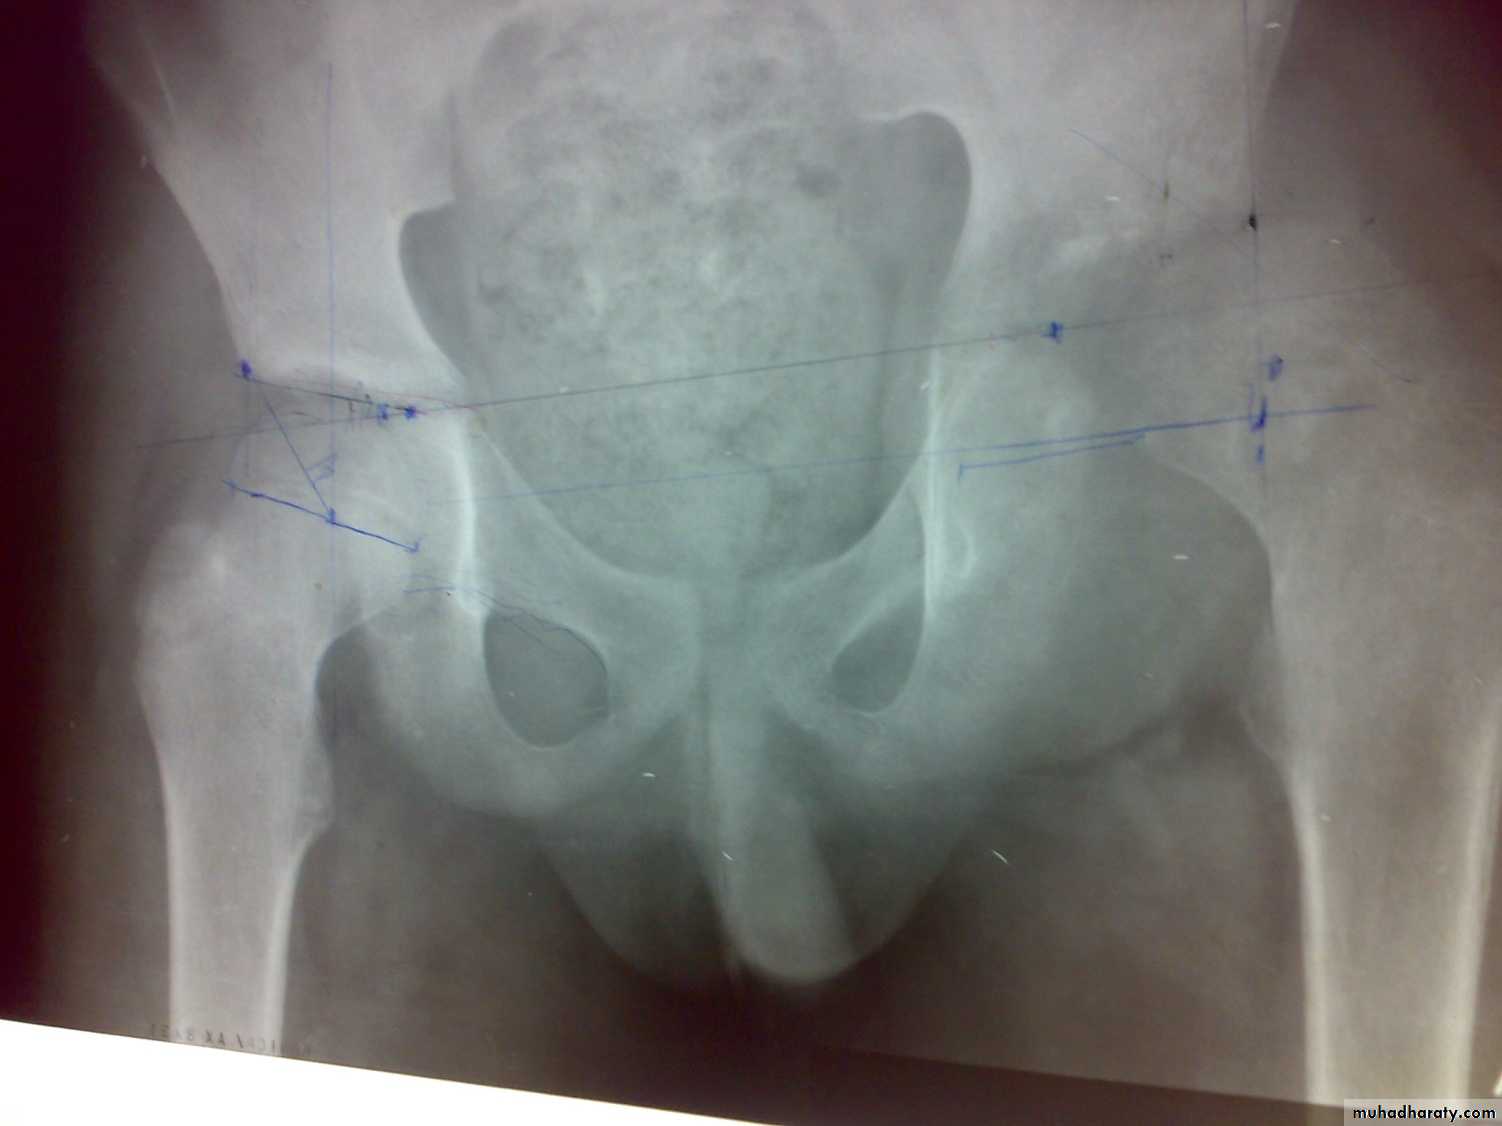

When microorganism virulence is low or the patient more resistant or both Subacute haematogenous osteomyelitis occur. The common microorganism is staph. aureus. Commonly affect distal femur or proximal tibia or distal tibia.

There is a well define cavity in metaphysis of long bone or in flat bone. The cavity contain acute and chronic inflammatory cell infiltration with fluid. Patient usually child had pain, limping, swelling and tenderness, there is no fever, WBCs is normal and ESR elevated.

X-ray show well- define, rounded or oval cavity surrounded by sclerosis( Brodies abscess)